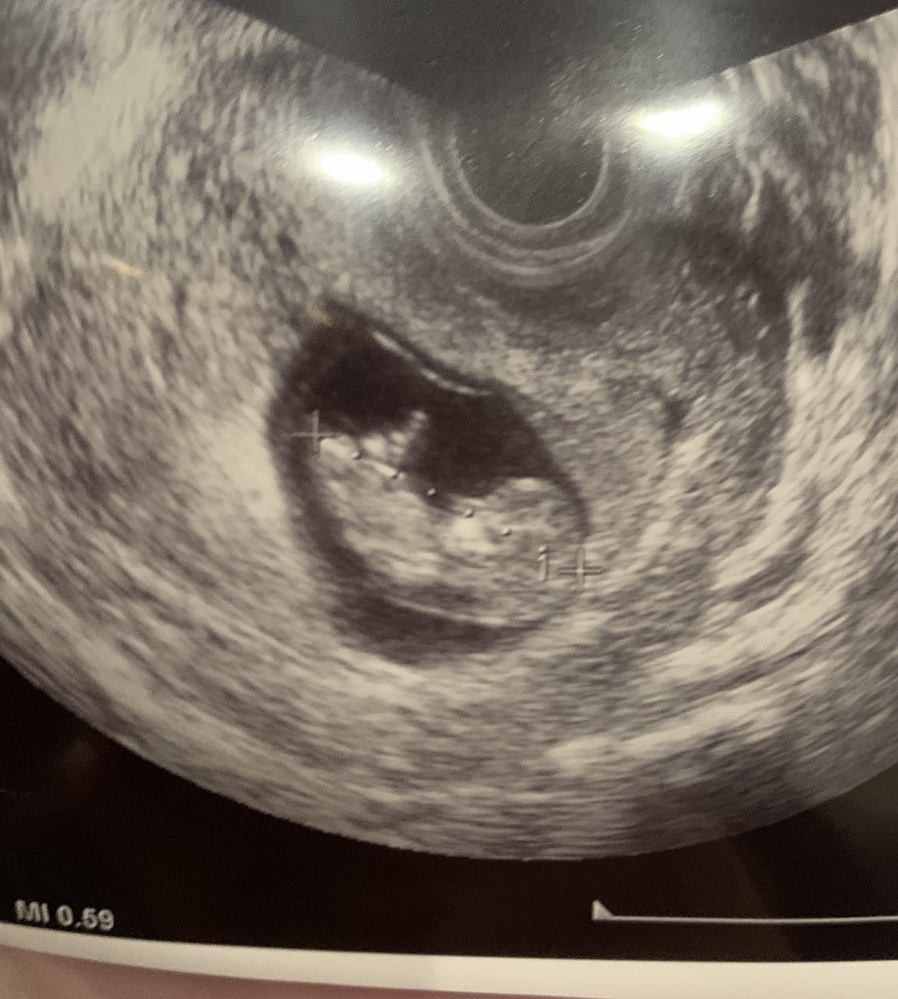

妊娠14週2日 14w2d の超音波 エコー 写真